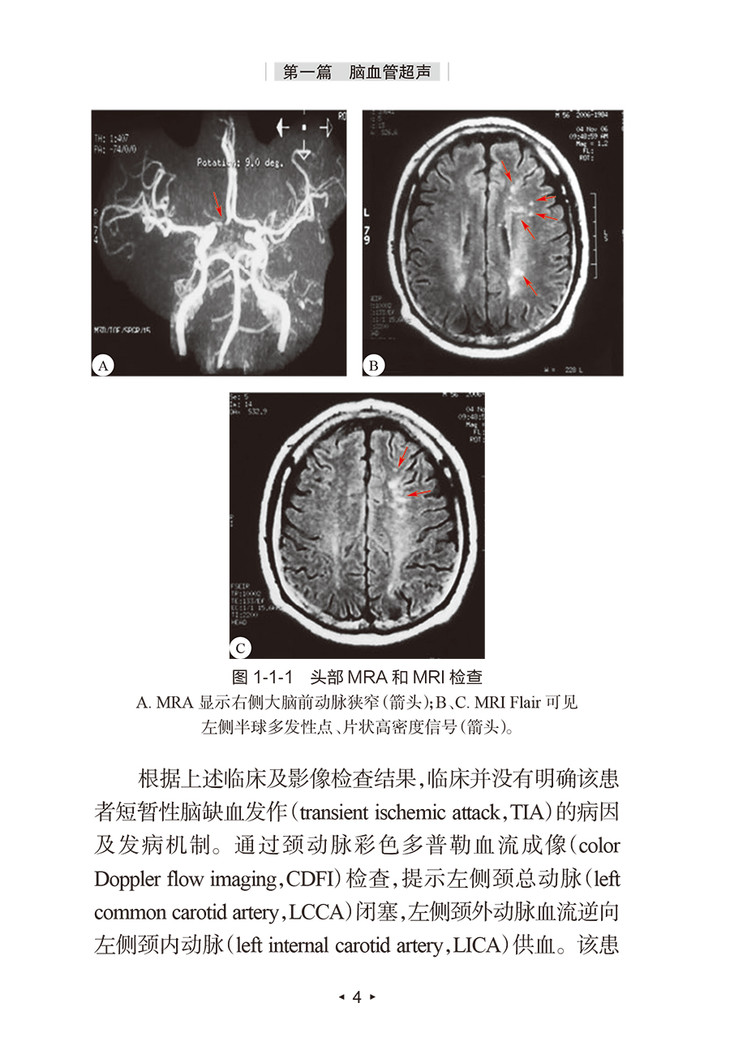

《脑卒中血管超声/脑卒中防治系列丛书》包括脑血管超声与颈部动脉超声两篇共十二章,概述了针对脑卒中相关病变的解剖学基础、脑血流动力学机制、超声检查方法与病变评估特征等。作为脑卒中防治系列丛书之一,希望该书能为临床专业医师针对脑卒中患者的整体化血管超声评估与临床诊疗带来新的理念,提高脑卒中患者超声检查及评估的准确率。